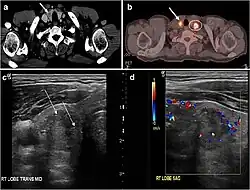

Fig. 7. A 51-year-old female patient post total thyroidectomy for PTC with elevated thyroglobulin measurement. an Axial non-enhanced CT scan of the neck at the level of the thyroid bed demonstrates a well-defined, rounded, homogenously dense soft tissue situated between the trachea and left internal jugular vein (white arrow). b Transverse ultrasound image of the neck demonstrates a well-defined, homogeneous, hypoechoic soft tissue nodule measuring 6 mm (white arrow) with no detected micro-calcifications. Biopsy showed a predominantly residual normal thyroid tissue with micro-foci of PTC.[1]

Fig. 8. A 48-year-old male patient post total thyroidectomy with PTC recurrence. a Transverse greyscale ultrasound of the neck demonstrates a left thyroid bed heterogeneous, predominantly hypoechoic irregular lesion with calcifications (white arrow). b A spot image of iodine 123 total body scan of the neck demonstrate a focus of abnormal radiotracer uptake at the left thyroid bed (Black arrows) between the annotated markers. c Enhanced axial CT scan of the neck demonstrates an enhancing large left thyroid bed mass (white arrow) with no calcifications. The lesion exerts a mass effect on the oesophagus (black arrow) and is inseparable from the trachea.[1]

Fig. 9. A 58-year-old male patient with persistence PTC at thyroid bed with hypervascular nodal metastasis. a–c Transverse greyscale and colour Doppler neck ultrasound demonstrate hypoehoic soft tissue in the left thyroid bed (white arrow in a). There are a heterogeneous enlarged lymph nodes at level 2 and 3 with markedly increased vascularity (white arrow in b and c). d–f Enhanced axial CT images of the neck demonstrate a 2.7 × 1.4 cm hypodense soft tissue lesion anterior to the left carotid sheath (white arrow). There are left-sided enhancing abnormal and enlarged lymph nodes at cervical level 2 and 3 (black arrows).[1]